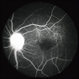

- Idiophatic new vasculitis

- optic disc leakage, diffuse vasculitis, intraretinal hemorrhage

- Idiophatic retinal vasculitis in a 45 year old woman